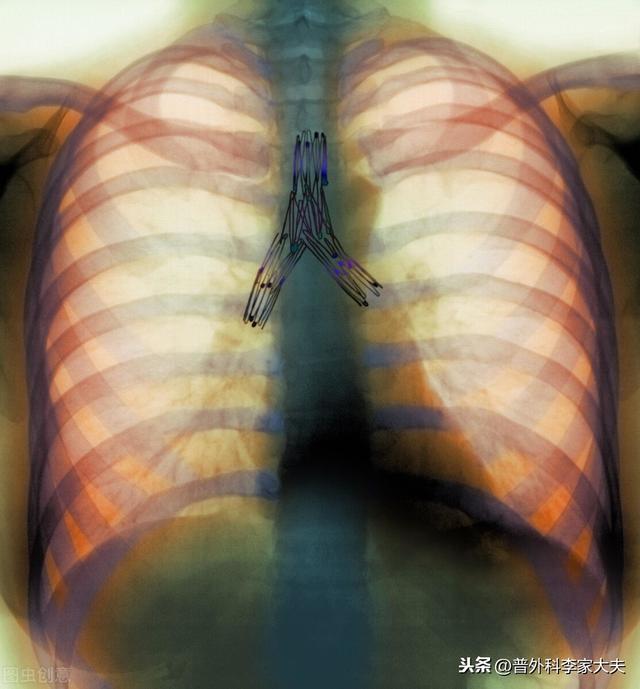

chirurgie pulmonaire par thoracoscopie

opération radicale du cancer du poumon

Endoprothèse bronchique